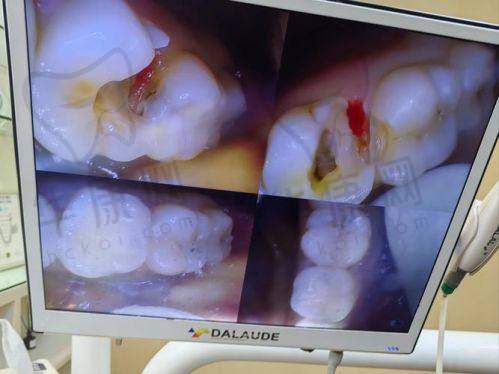

有一位患者因后牙龋坏重度,来到西安弗莱堡口腔就诊。医生为其采用了3MP60树脂补牙,整个治疗过程顺利。补完牙后,患者的牙齿修复了正常的咀嚼功能,而且外观上与天然牙齿无异。经过一段时间的回访,患者表示补牙成效非常好,没有出现任何不适症状,对此次补牙体验十分满意。